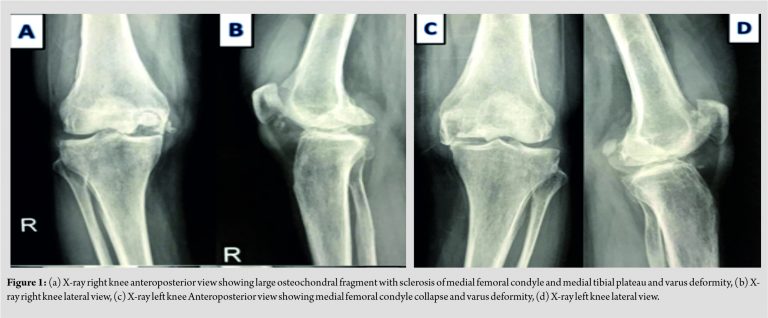

A 45-year-old female patient presented to us with pain in both the knees since 1 year. She also had difficulty in walking. Pain had gradually increased over the period of 1 year. She had no history of the previous trauma, steroid use, meniscus surgery, alcohol intake, or smoking. Physical examination revealed local tenderness over MFC and medial tibial condyle and decreased range of motion. Laboratory investigations showed no specific findings. Subchondral fracture with articular surface collapse of MFC with joint space narrowing and varus deformity was seen on X-ray in both the knees. Sclerosis was seen on X-ray in the medial tibial condyle on both the sides. X-ray of both knees revealed SPONK in Koshino’s Stage IV and Carpintero’s Stage IV (Fig. 1).